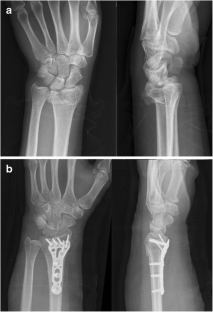

Fig. 1

Fig. 2